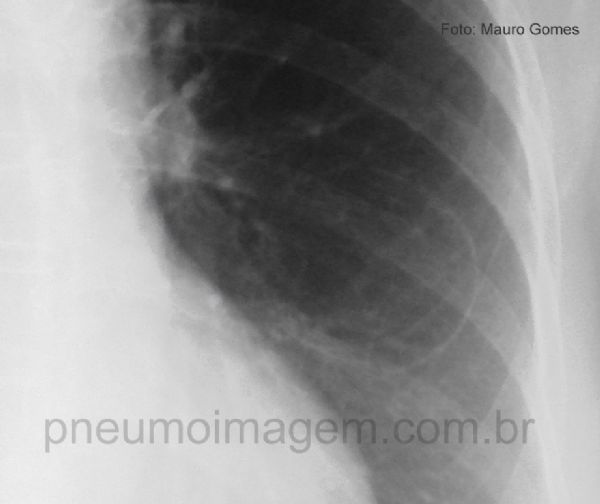

Cisto broncogênico faz parte de um espectro de anomalias congênitas do pulmão que inclui seqüestro pulmonar, malformação adenomatóide cística congênita e

hiperinsuflação lobar congênita. Observe a fina linha circular que delimita área de maior transparência (seta) e poderia ser confundida com uma bolha.

Detalhe da radiografia em PA mostrando a fina linha circular que delimita área de maior transparência. Os cistos broncogênicos decorrem da brotação anormal da árvore brônquica primitiva, o que ocorre entre os dias 26 e 40 de gestação. O diagnóstico diferencial deve ser feito com bolha e, quando possui nível líquido, com abscesso pulmonar.